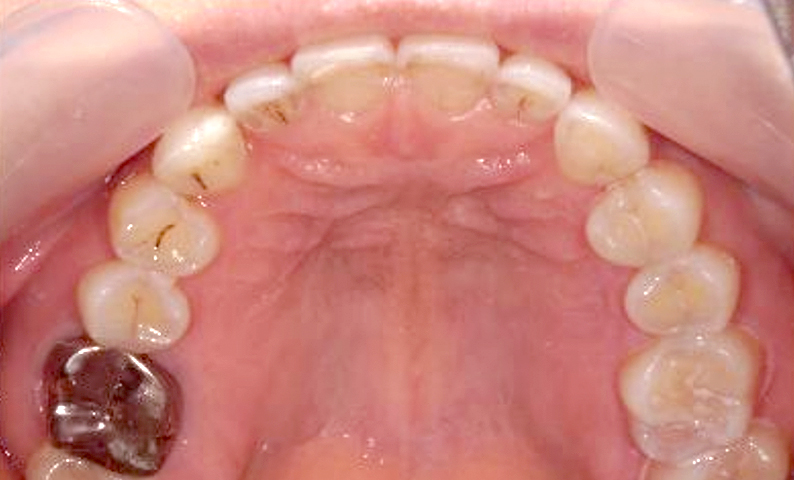

すきっ歯の種類

- 正中離開(せいちゅうりかい)

:前歯だけに隙間がある状態 - 空隙歯列(くうげきしれつ)

:全体的に歯に隙間がある状態